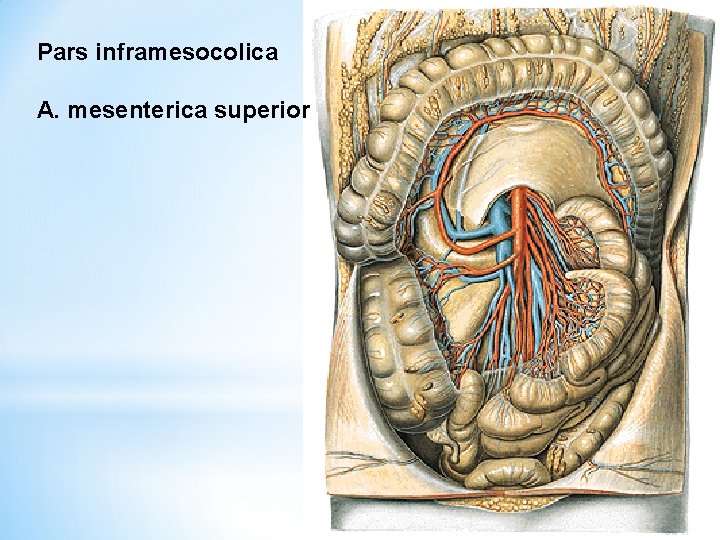

Pars inframesocolica A. mesenterica superior